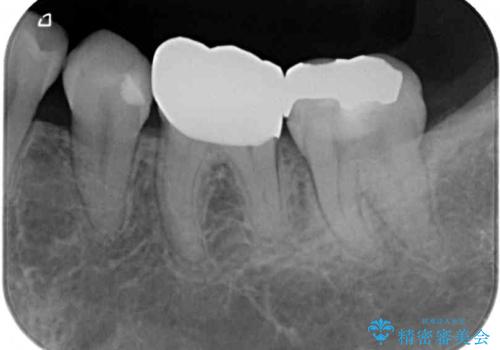

- 奥歯の詰め物や周辺の歯が欠けてしまったとのことで来院された患者様です。

上顎は、元々の詰め物が小さく、欠けた範囲も大きくなかったため、セラミックインレーにて修復治療を行うこととしました。

一方下顎は、元々のむし歯の範囲が広かったため、長期的な予後を踏まえ、セラミッククラウンにて補綴治療を行うこととしました。